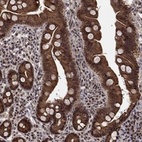

Immunohistochemical staining of human duodenum shows strong nuclear, cytoplasmic and membrane positivity in glandular cells.